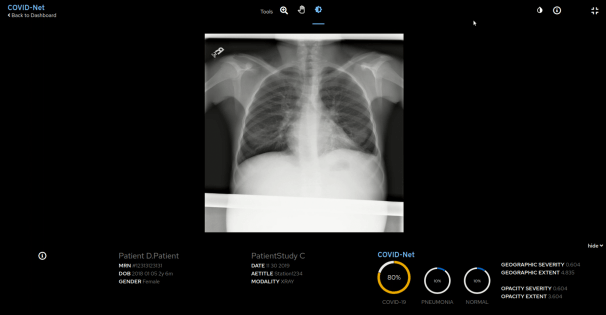

Red Hat, leverancier van open sourceoplossingen, kondigen een samenwerking aan om de implementatie van COVID-Net bij ziekenhuizen en andere zorginstellingen te versnellen. Deze suite van

Het doel van deze samenwerking is om het voor clinici makkelijker te maken om COVID-Net in ziekenhuizen te gebruiken door middel van een webgebaseerde grafische gebruikersinterface (GUI). Deze wordt met behulp van

Red Hat OpenShift - een enterprise Kubernetes-platform dat implementaties binnen complexe hybride en multicloudinfrastructuren ondersteunt - bovenop het

Boston Children's ChRIS-framework aangeboden.